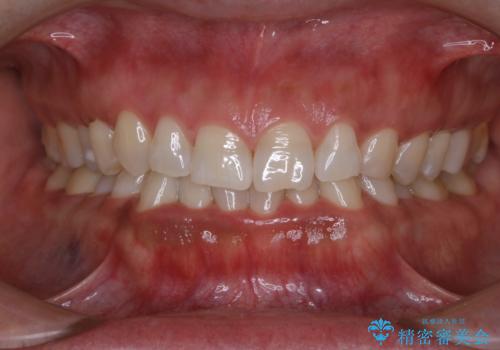

- インビザラインで矯正治療中にクリーニングを希望されました。PMTC60分コースで、クリーニングと歯ブラシ指導を行いました。

磨けているようでも、染出しをして目に見えるプラーク(歯垢)を確認することで、より正しいブラッシング方法を身につけることができます。インビザライン中は、歯にアタッチメントをつけるため、歯の表面がデコボコしてプラークが付きやすい状態になります。毎日のケアでしっかりと汚れを落として虫歯や歯周病・口臭のリスクを減らしていくことが大切です。定期的にメンテナンスを行い、ケアがどれくらい出来ているか確認したり歯科医院で専門的な機械や器具によるPMTCを行うことをおススメします。